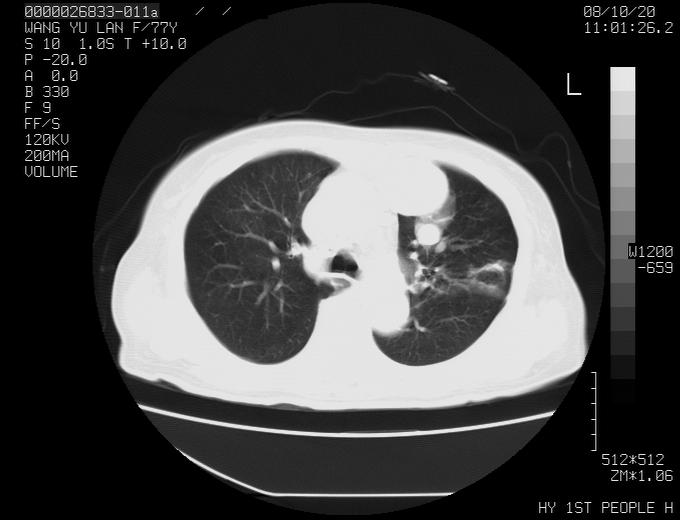

女性,77岁,胸部疼痛半月。左上肺团块影,本人考虑血管畸形,请分析

非常典型的avm(谢谢楼主,收藏了)

左上叶前段多发结节肿块并前段支气管息肉样结节、上叶腋亚段阻塞性肺炎,以结核可能性大。

纵隔有多个淋巴结肿大,提示周围型肺癌并转移可能性大。

1、考虑avm可能性大。2、纵隔有肿大淋巴结,左肺上叶有炎性病变,不排除肺癌并转移可能。